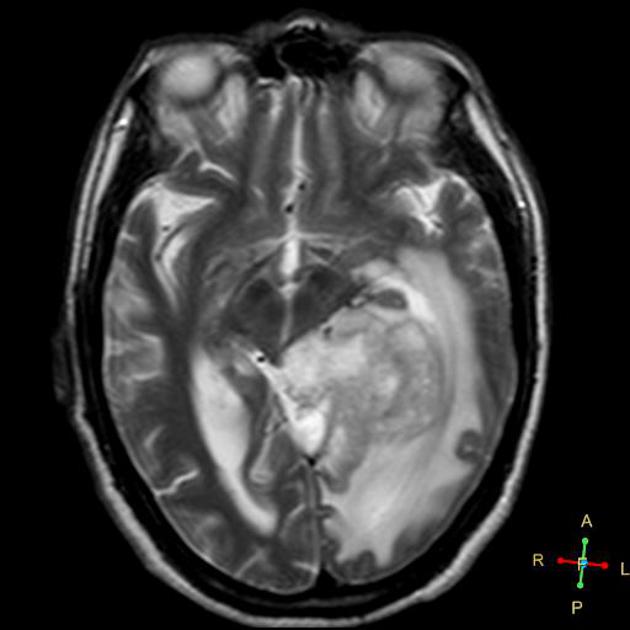

After a careful H&P with attention to neurologic symptoms, time of onset and rate of increase, imaging is critical to localization and diagnosis. Surgery, including a complete debulking if possible is the first line treatment, and sets the stage for the next step. Imaging is predominantly MRI based, with T1 ±gad, T2, FLAIR, diffusion weighted, and gradient echo sequences to identify and localize the extent of disease. Surgery is used to debulk the tumor completely if possible, and if not to obtain tissue for diagnosis.

Imaging

GBM T2

Radiotherapy General Fields

The treatment fields for HGG in pediatrics, similar to adults is the imaging enhanced region plus a margin. The initial GTV is the MRI T2 abnormality (edema). The initial CTV = GTV + 1.5 cm, corrected for anatomical barriers. The usual dose to this volume is 50.4 - 54 Gy at 1.8 Gy/fraction. The second GTV (boost GTV) is the T1+gadolinium enhancement. The second CTV=GTV+1 cm. This is then carried to 59.4 Gy.

• initial GTV = T2 or FLAIR mri image

• The CTV is the T2 GTV+1.5 cm margin, with corrections for anatomical barriers (⇒ 50-54 Gy)